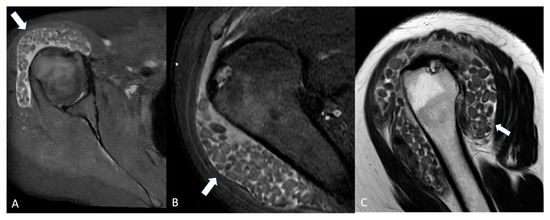

A typical cystic shoulder bump is the “geyser sign” (GS) (Figure 1), a characteristic imaging finding associated with chronic rotator cuff tears and degenerative changes in the acromioclavicular (AC) joint capsule. This sign is visualized as a fluid-filled collection above the AC joint, extending from the subacromial bursa through the compromised AC joint capsule into a subcutaneous space above the clavicle [16].

Figure 1.

(A) Elderly woman with a soft bump on the cranial portion of her right shoulder (black arrow). (B) coronal STIR and (C) sagittal T1-weighted showing a cystic lesion superior to the acromion-clavicular joint (white arrows). The lesion is raising subcutaneous soft tissue. Acromioclavicular osteoarthritis is noted (black arrowhead).